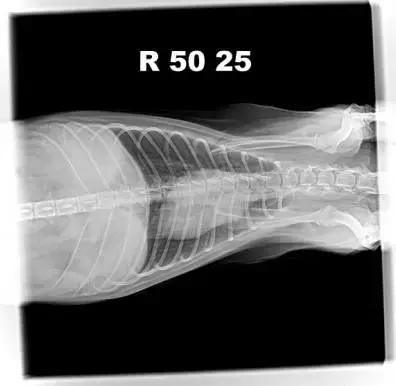

2.4.1 胸腔DR

胸腔DR腹背位/右侧位检查,影像未见明显异常。

25日腹背位胸腔DR影像

25日右侧位胸腔DR影像